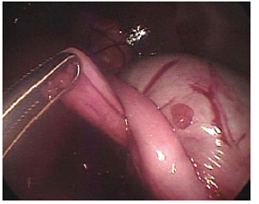

Six New Zealand rabbits (Oryctolagus cuniculus), between 2.5 and 3.5 kg of weight were used. Animals were laid supine with a 15° anti-Trendelenburg position, and access ports were established. A first port was placed in the midline, between the last two pairs of mammary glands, where a 10 mm trocar for the lens was introduced by blunt dissection (Hasson technique). A 0° telescope was used. The abdomen was insufflated through this port reaching a 10mmHg pressure. Once intra-abdominal vision was achieved, three additional 3 mm ports were established, one slightly cranial to the right and two slightly cranial to the left of the telescope (Fig. 1). The stomach, hiatal region and esophagus were identified. Conventional surgical instruments, such as Maryland forceps, needle holders and scissors, were used for the procedures. The surgeon utilized the two 3 mm ports located immediately adjacent to the telescope. In addition to handling the lens, the surgical assistant helped the surgeon with the esophagus dissection by using the farthest port from the left side, in order to restrain the stomach with forceps at the antrum. The stomach was pinched with forceps at the antrum to create traction. The esophagus was then dissected and separated from the diaphragmatic cruras. Care was taken to preserve the vagus nerves. The gastric fundus was subsequently passed behind the esophagus, and a 360º “floppy” Nissen fundoplication fixed with three surgical knots was performed using a 3-0 poliglactin 910 suture. All animals were euthanized after surgery completion, and digestive tract patency and presence of leaks were assessed. Next, surgically concerned organs were resected for histopathological examination (Fig. 2).